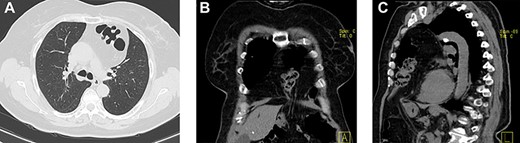

She had a chest X-ray done (Fig. 1) that showed widening of the mediastinum, as well as a few air-fluid levels, which raised suspicion of a diaphragmatic hernia. She also had a thoracic CT done (Fig. 2) that revealed a large hernia in the anterior mediastinum, containing transverse colon and a significant amount of ‘omentum,’ causing right side heart deviation.

(a–c) Axial, coronal and sagittal images, respectively, of thoracic and abdominal CT showing the localization of this hernia.

Thoracic CT is the gold-standard imaging study for determination of the content and localization of the ‘foramen’ of its hernia. Currently, urgent thoracic CT has been more frequently requested, so as to clarify some respiratory conditions, which has allowed us to detect asymptomatic diaphragmatic hernias, and properly refer these patients to surgery. It has been estimated that the diameter of the defect may grow up to 7 mm per year, if left untreated [8].